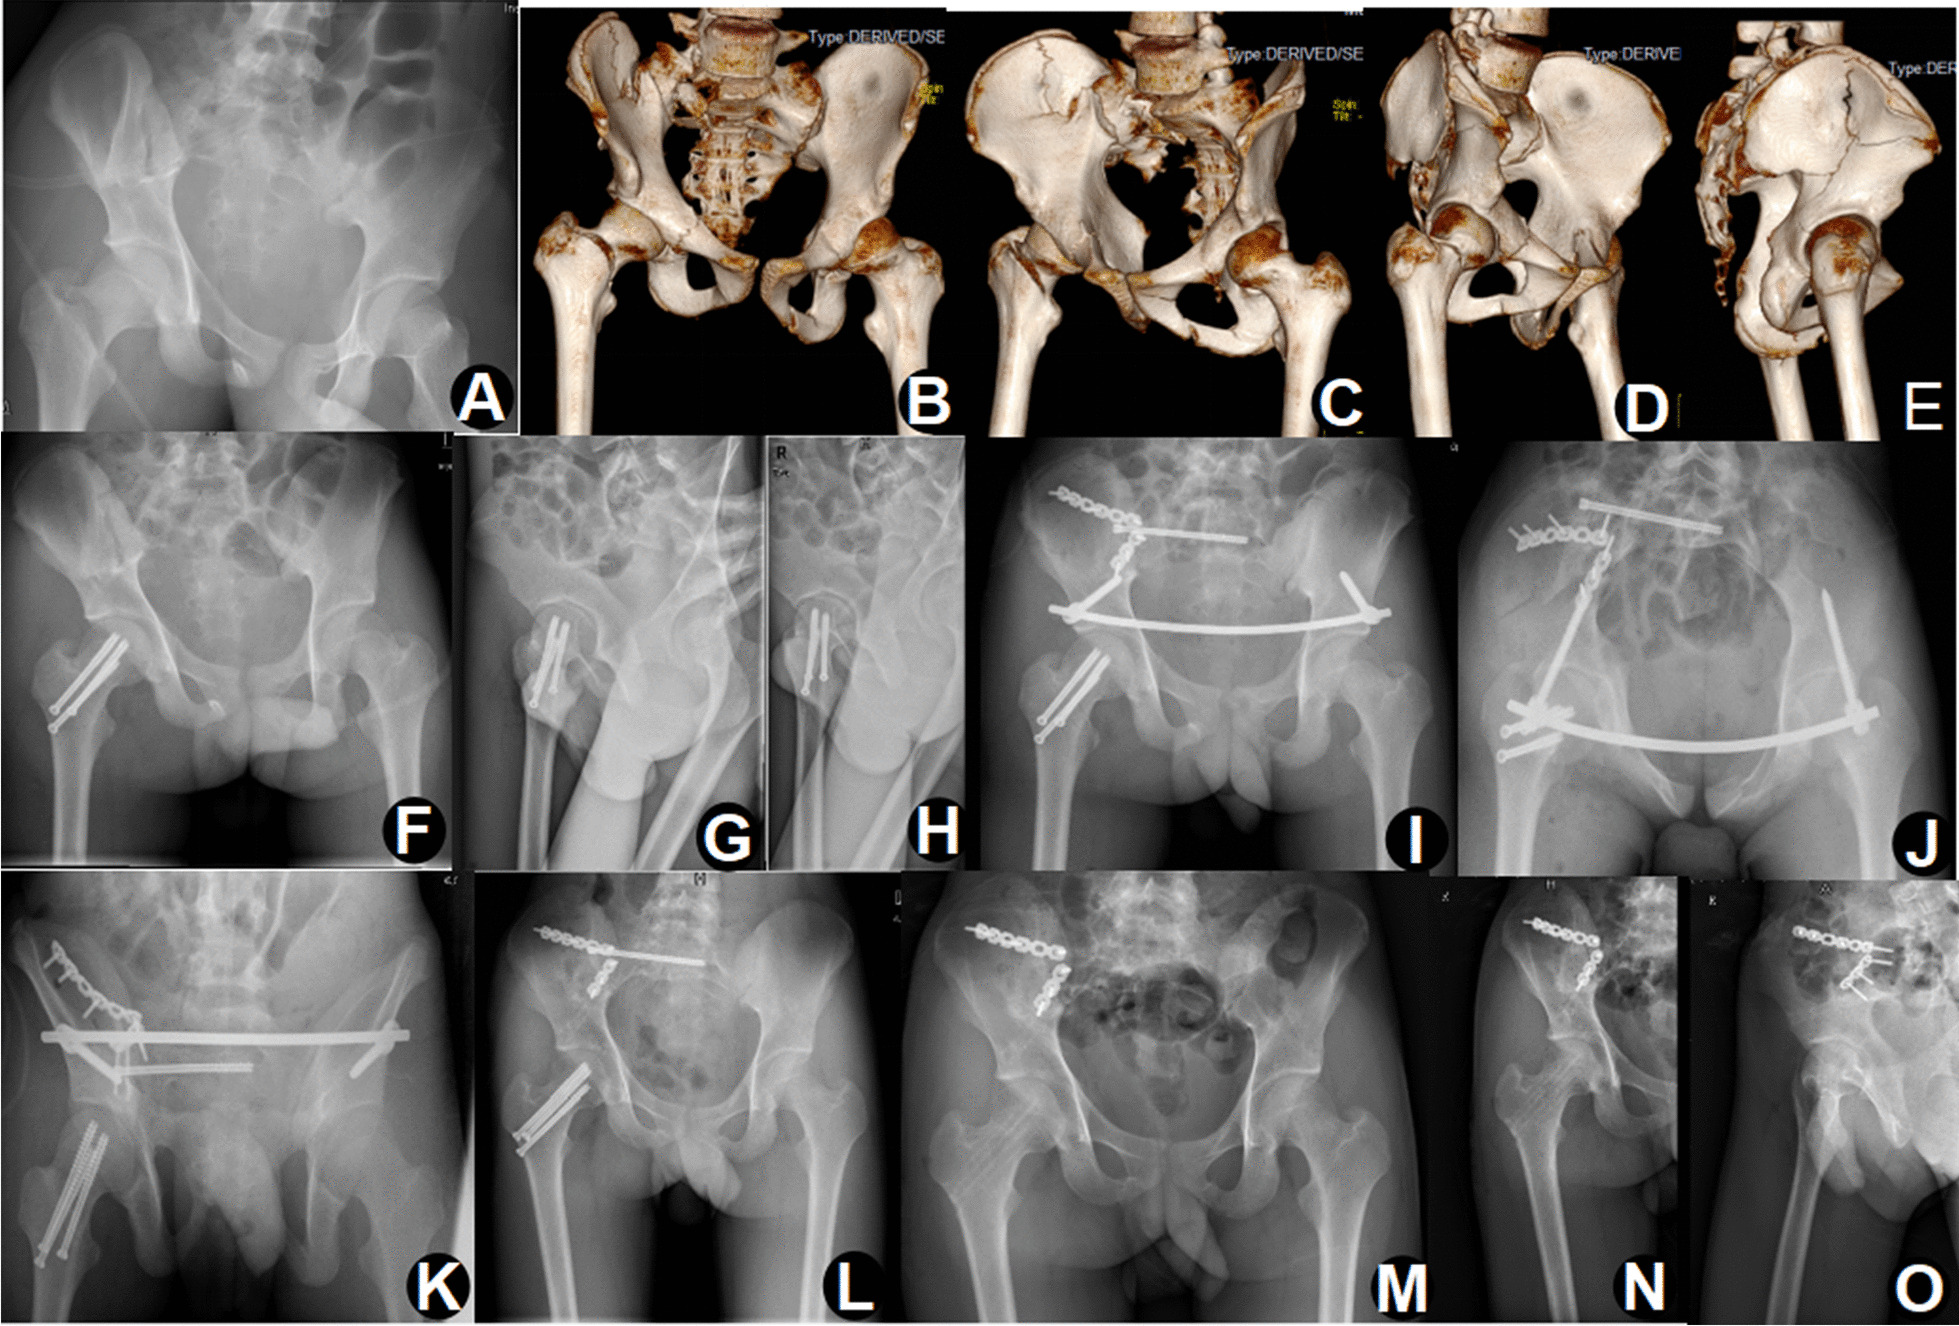

Fig. 2.

A 16-year-old male treated with damage control orthopaedics. Initial radiographs (A) and three-dimensional computed tomography images (B–E) showing a type C floating hip. Closed reduction and internal fixation of femoral neck fracture on the third day after admission (F–H). Percutaneous sacroiliac screw fixation of the posterior ring, INFIX fixation of the anterior ring, and anterior fixation of the acetabular fracture by the lateral window of the IL approach on the tenth day (I–K). The removal of INFIX 1 year after surgery (L). The removal of cannulated screws and sacroiliac screw 1.5 years after surgery (M–O)